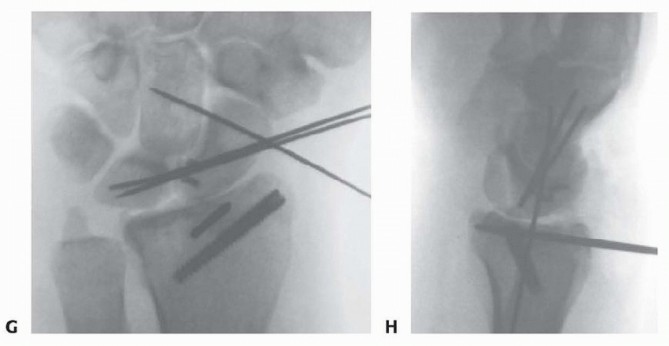

TECH FIG 2 • (continued) G,H. PA and lateral radiographs showing anatomic reduction to the impacted scaphoid facet fracture. (The tear of the SLIL also was acutely repaired.) Use a bone tenaculum to further diminish the gap between the radial styloid and lunate facet fragments. Place guidewires transversely under the subchondral surface of the radius from the radial styloid into the anatomically reduced lunate facet fragment. It is important to pronate and supinate the wrist following placement of the transverse pins to ensure the guidewires have not violated the DRUJ. The concave nature of the DRUJ makes radiographic assessment difficult. Consider insertion of bone graft to support the reduced lunate fragment and avoid late settling. Make a small incision between the fourth and fifth dorsal compartments. Use cancellous allograft bone chips or bone substitutes. If feasible, place headless cannulated screws to stabilize both the radial styloid and the impacted lunate facet fragments ( TECH FIG 2E-H). 2. ## Three-and Four-Part Fractures with Metaphyseal Comminution A combination of open surgery, using a volar plate for stability, and arthroscopy, as an adjunct to assist the articular reduction, is used if metaphyseal comminution is present ( TECH FIG 3). Volar plate stabilization is very stable and allows for early range of motion and rehabilitation as compared to K-wires or headless screws alone.

---